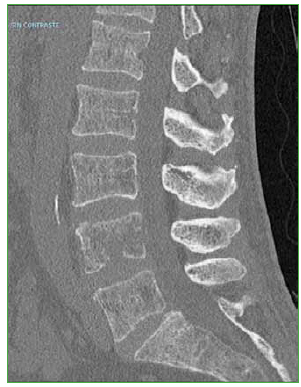

Las hernias discales intraesponjosas vertebrales o nódulos de Schmörl consisten en una herniación o una extrusión del núcleo pulposo del disco intervertebral a través del platillo vertebral hacia el cuerpo adyacente. Suelen asociarse a deformidades vertebrales, como la enfermedad de Scheuermann, o a enfermedades reumáticas, como la espondilitis anquilopoyética. En general, son hallazgos casuales y cuadros asintomáticos; son pocos los casos publicados de nódulos sintomáticos. Su aparición estaría relacionada con un platillo vertebral debilitado por traumatismo o estrés repetido. Cuando el nódulo es agudo o reciente, puede ser difícil diferenciar la degeneración benigna de una infiltración maligna o una infección. Presentamos un caso inusual de un nódulo de Schmörl doloroso en un hombre sin antecedentes de relevancia, que enmascaró una lesión metastásica de carcinoma pancreático a nivel lumbar. Se realiza una revisión bibliográfica. ABSTRACTIntraosseous disc herniation –or Schmörl nodes (SN)– are a herniation or prolapse of the nucleus pulposus of the intervertebral disc through the vertebral plate and into the adjacent vertebral body. They are usually associated with vertebral deformities, suchas Scheuermann’s disease, or rheumatic diseases, such as ankylopoietic spondylitis. In general, they are spontaneous and asymptomatic findings, and there are only a few reported cases of symptomatic nodes. The etiology is supposedly related to a weakened spinal plate due to trauma or repeated stress. When the node is acute or recent, it can be difficult to differentiate a benign degeneration from a malignant infiltration or infection. In this paper, we discuss the unusual case of a painful Schmörl node in a man with no relevant history and a masked metastatic lumbar spinal tumor originated from pancreatic cancer. We performed a literature review.Descargas